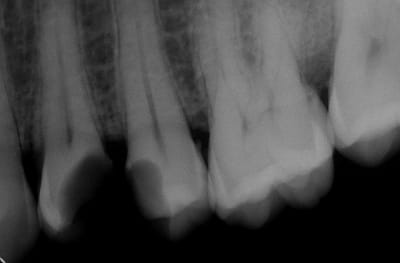

Voici les photos toutes fraiches de ce matin.

Vos critiques sont bien sur les bienvenues je dois encore beaucoup m'améliorer sur les prises de teintes, et je m'y attelle en ce moment,, par contre en ce qui concerne la pérennité de la restauration…..ma patiente a sa dent bien vivante, aucun joint sous gingival , possibilité de réaliser une endo dans le futur sans détruire la restauration existante si besoin, possibilité re refaire un onlay dans quelques années si ça casse, toujours sur dent vivante…. bref la liste des avantages est très longue par rapport au classique endo-IC-CCM.